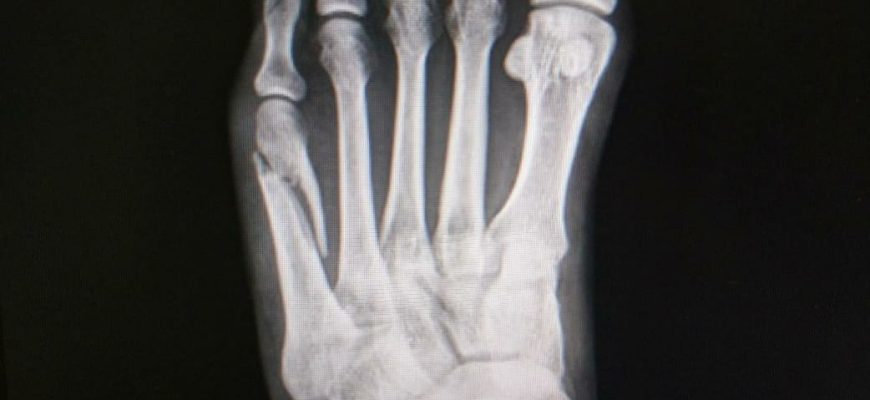

Анатомия плюсневых костей: Форма и функция Плюсневые кости играют ключевую роль в нашем организме, обеспечивая возможность движения и поддерживая структуру стопы.

Анатомия плюсневых костей: ключевые особенности и их роль в движении Когда мы думаем о стопе, часто представляем её как сложную и многоразличную структуру

Анатомия плюсневых костей: ключ к пониманию строения стопы Когда мы задумываемся о здоровье нашей стопы, зачастую волнуются о травмах, боли или правильной